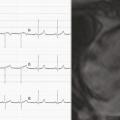

La patiente était adressée en cardiologie. Dans le contexte de son antécédent de cancer, d’une dyspnée aiguë et d’une élévation des D-dimères (3 120 ng/L), une angio-tomodensitométrie thoracique avait été prescrite, qui n’avait pas montré d’embolie pulmonaire mais des opacités bilatérales pseudo-nodulaires compatibles avec une surcharge vasculaire. À son arrivée, la patiente était cliniquement stable. Sa pression artérielle était mesurée à 116/94 mmHg, sa fréquence cardiaque à 100 batt/min, une saturation à 99 % sous 2 L d’O2, sa température était mesurée à 37,1 °C. L’électrocardiogramme (ECG) [fig. 2 ] montrait des ondes T négatives dans le précordium.

La patiente était adressée en cardiologie. Dans le contexte de son antécédent de cancer, d’une dyspnée aiguë et d’une élévation des D-dimères (3 120 ng/L), une angio-tomodensitométrie thoracique avait été prescrite, qui n’avait pas montré d’embolie pulmonaire mais des opacités bilatérales pseudo-nodulaires compatibles avec une surcharge vasculaire. À son arrivée, la patiente était cliniquement stable. Sa pression artérielle était mesurée à 116/94 mmHg, sa fréquence cardiaque à 100 batt/min, une saturation à 99 % sous 2 L d’O2, sa température était mesurée à 37,1 °C. L’électrocardiogramme (ECG) [